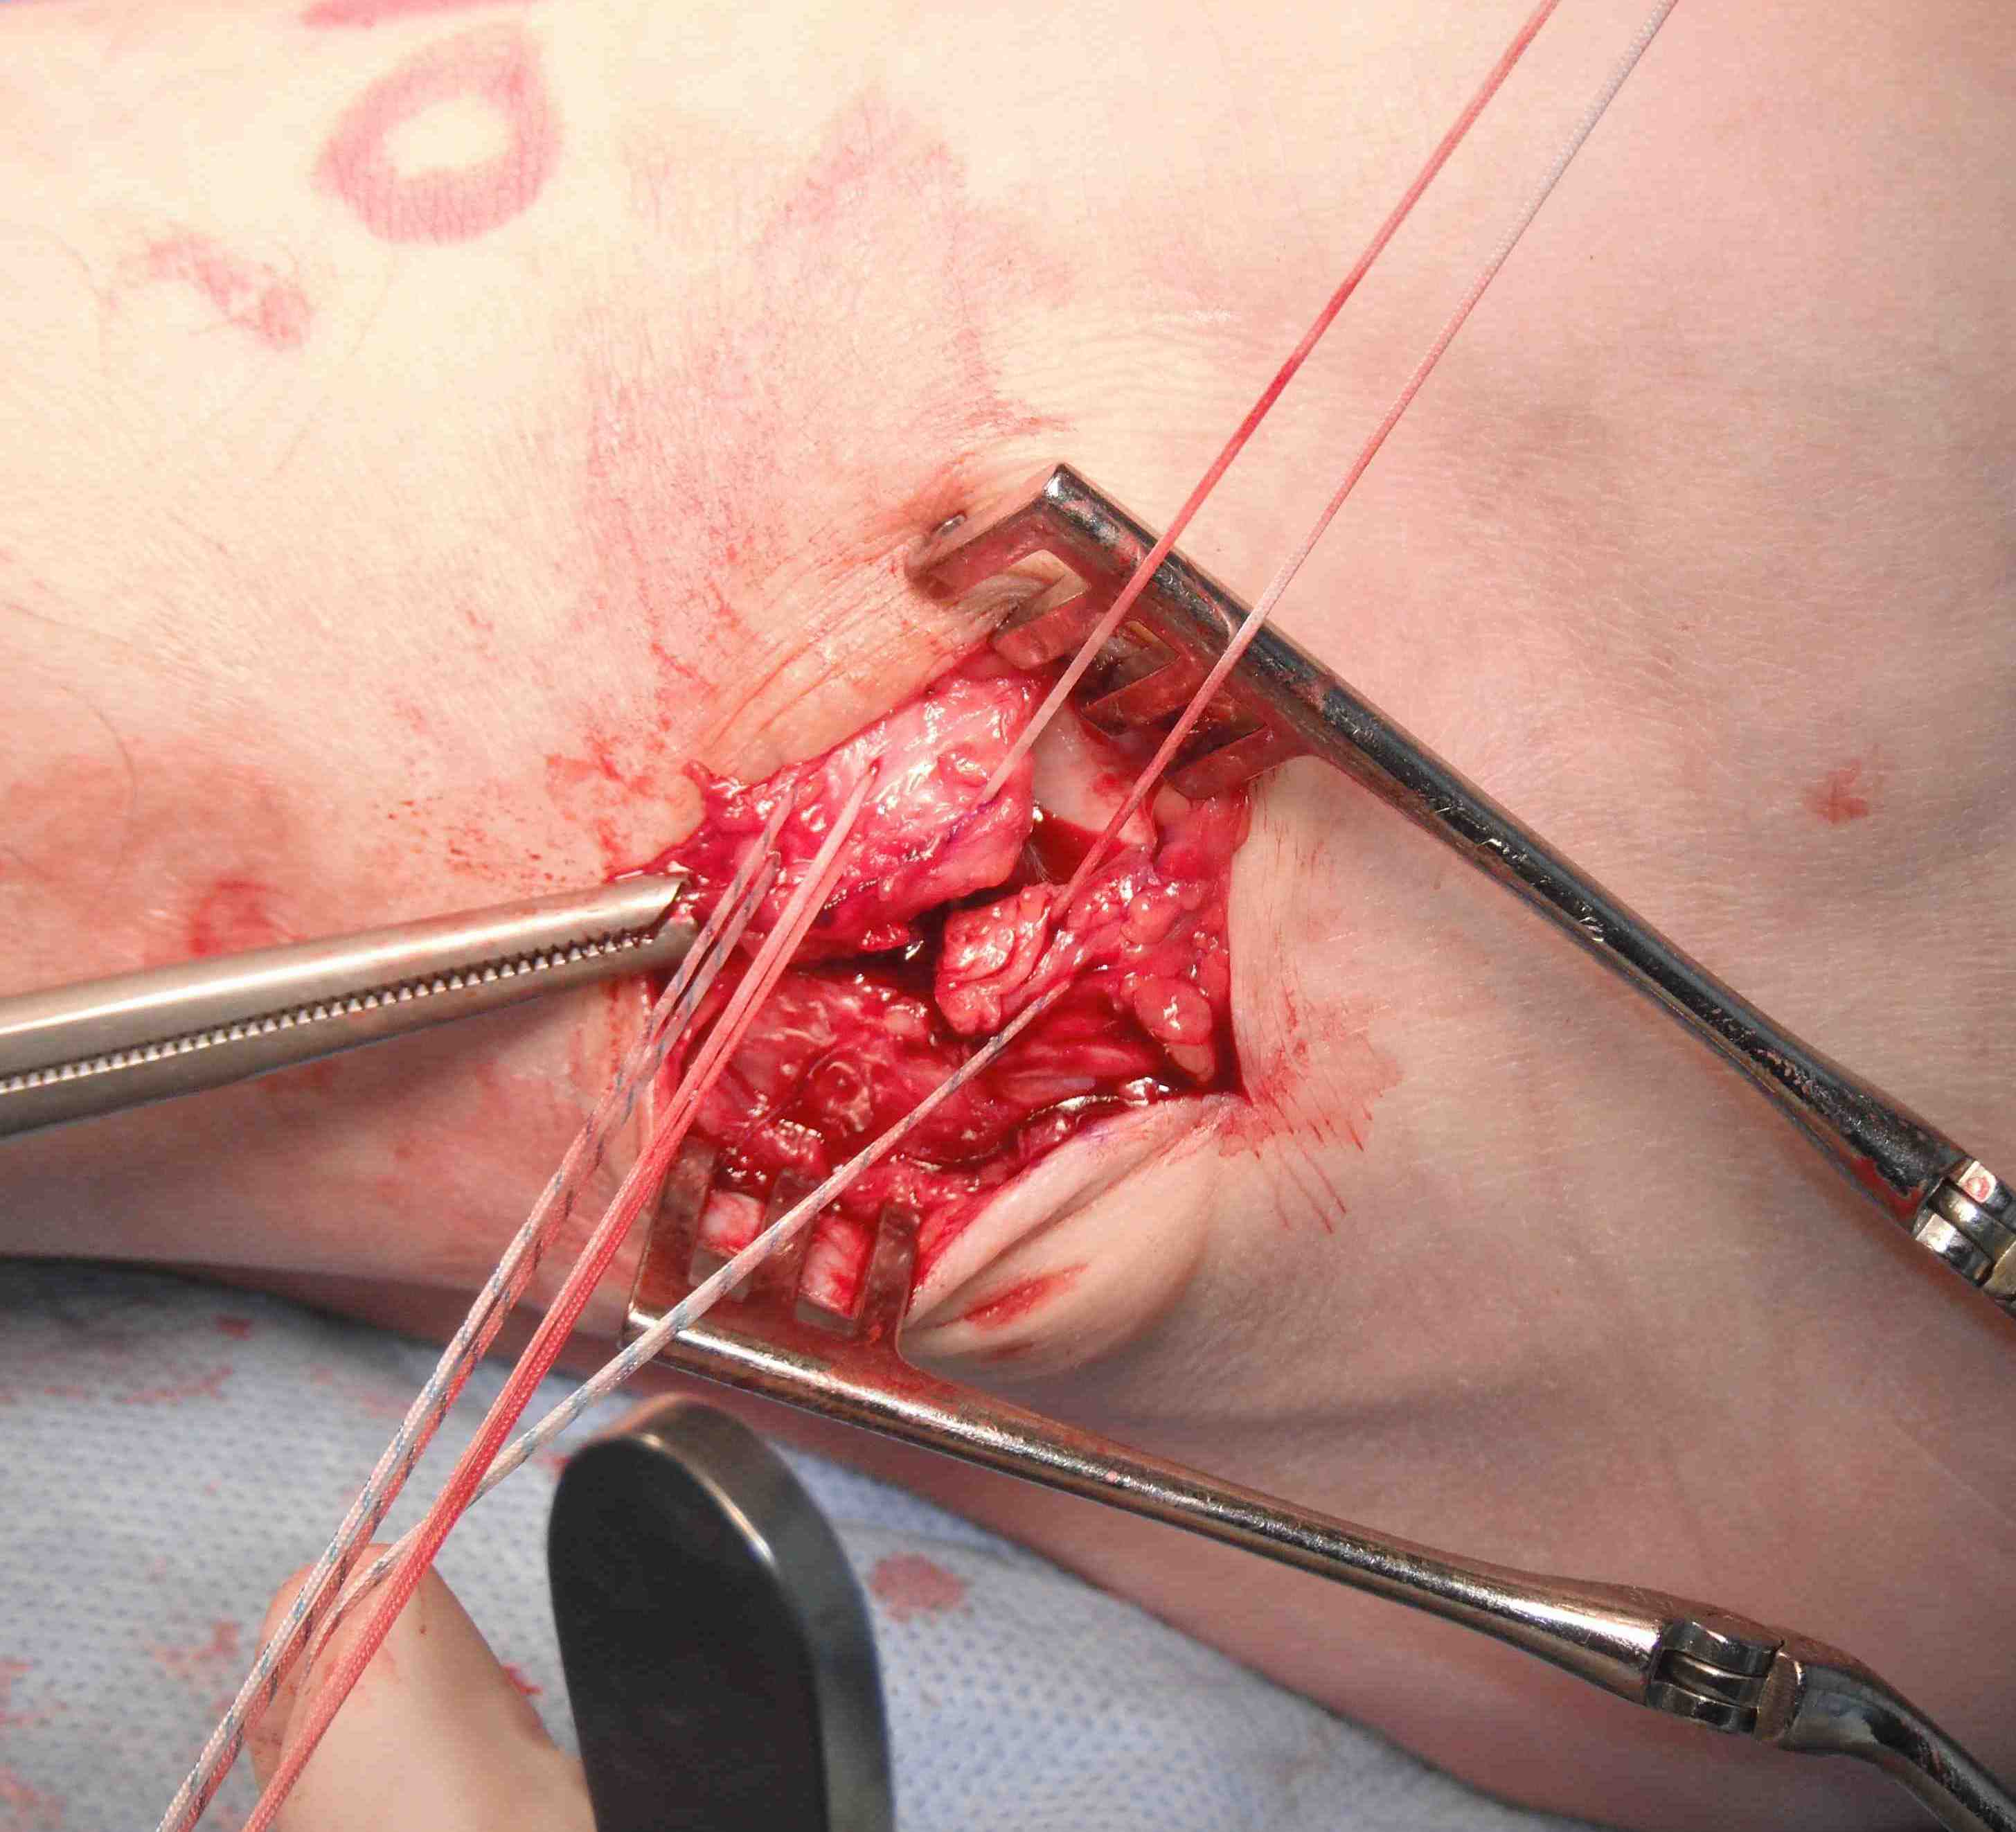

Open technique

Longitudinal incision anterior to lateral malleolus

- protect branches of superficial peroneal nerve

- expose tissue of ATFL / CFL

- anterior incision between ATFL and CFL to talus

- begins at tip of fibula to talus

- take off fibula as broad / thick flap

- superior flap is ATFL / inferior flap is CFL

- need to protect peroneals with inferior portion of dissection

- inspect talus for chondral damage

Place foot in eversion and AJ neutral

- 2 x 3.5 mm anchors in fibula

- ensure not in joint and not prominent

- 4 sutures through ATFL

- 2 through CFL

- 2 sutures either side of interval of ATFL and CFL

Gould modification

- advance the inferior retinaculum and suture to the fibular to reinforce the repair